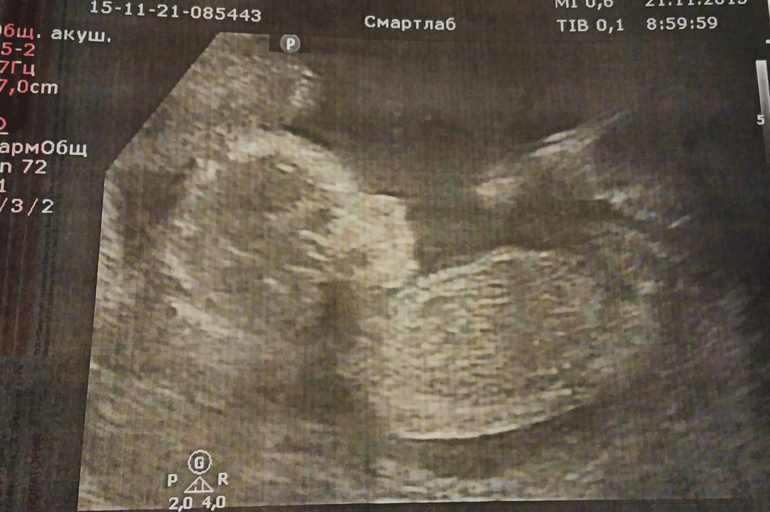

УЗИ, КТГ, доплер21.11.2015 второй раз увидела на УЗИ ребеночка! И сразу же, в первую секунду, сказали, что это ДЕВОЧКА! Мы безумно рады

. Муж очень хотел девочку, и я уже так привыкла к этому. 18 недель, соответствует сроку, всё в порядке! Я очень переживала из-за сильного тонуса, но после УЗИ он начал проходить.

Сначала малышка спала, но потом даже помахала ручкой

. Узистка попалась очень хорошая, уделила много внимания, около получаса! Показала все внутренние органы, смотрела сосуды мозга, кровоток. Слушали сердечко - 157 ударов! Вес целых 208 гр.

Сделала пару фотографий на память))) Вообще я получила море удовольствия, столько эмоций... считала пальчики, а она такие позы смешные принимала - то лицо ручками закрывала, то одну руку под голову подкладывала, то палец сосала... Единственное, что почему-то не сказали рост.